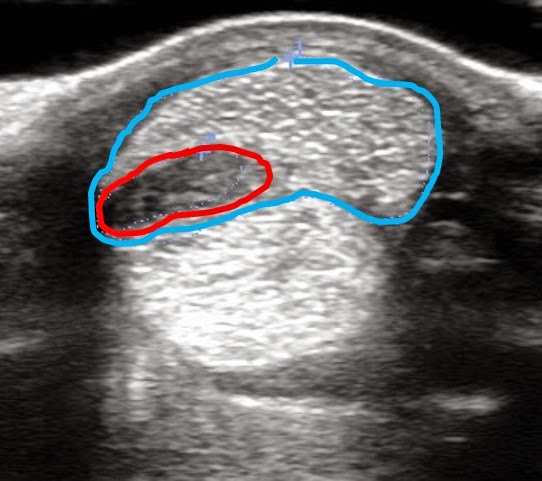

Callie’s Deep Digital Flexor Tendon (‘Bowed Tendon’) Injury | HorseDVM

Callie’s Deep Digital Flexor Tendon (‘Bowed Tendon’) Injury | HorseDVM

Callie’s Deep Digital Flexor Tendon (‘Bowed Tendon’) Injury | HorseDVM

Callie’s Deep Digital Flexor Tendon (‘Bowed Tendon’) Injury | HorseDVM

Callie’s Deep Digital Flexor Tendon (‘Bowed Tendon’) Injury | HorseDVM

Callie’s Deep Digital Flexor Tendon (‘Bowed Tendon’) Injury | HorseDVM

Callie’s Deep Digital Flexor Tendon (‘Bowed Tendon’) Injury | HorseDVM

Callie’s Deep Digital Flexor Tendon (‘Bowed Tendon’) Injury | HorseDVM

Callie’s Deep Digital Flexor Tendon (‘Bowed Tendon’) Injury | HorseDVM

Callie’s Deep Digital Flexor Tendon (‘Bowed Tendon’) Injury | HorseDVM

Callie’s Deep Digital Flexor Tendon (‘Bowed Tendon’) Injury | HorseDVM